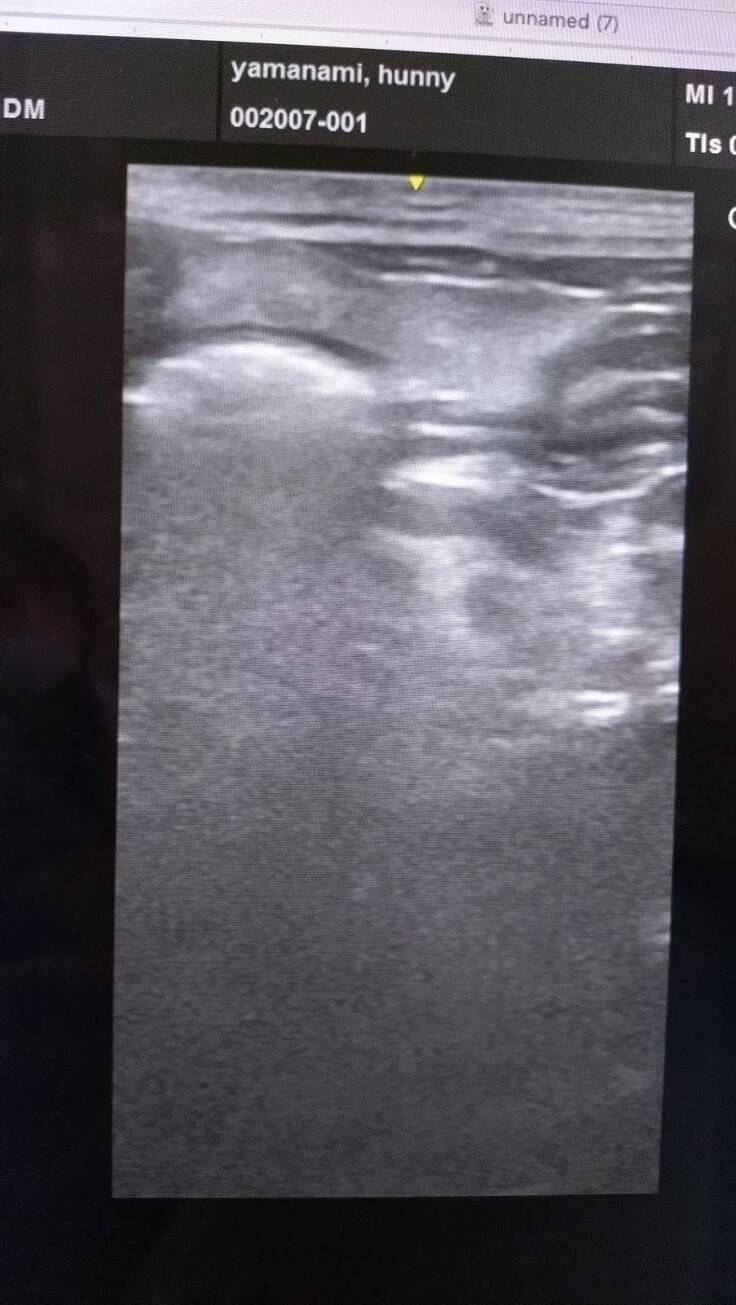

エコーをし、腹膜炎を起こし、腹水が溜まってる事が分かった😢

腸管白い

脂肪細胞も白い

腸の蛇行

→炎症反応